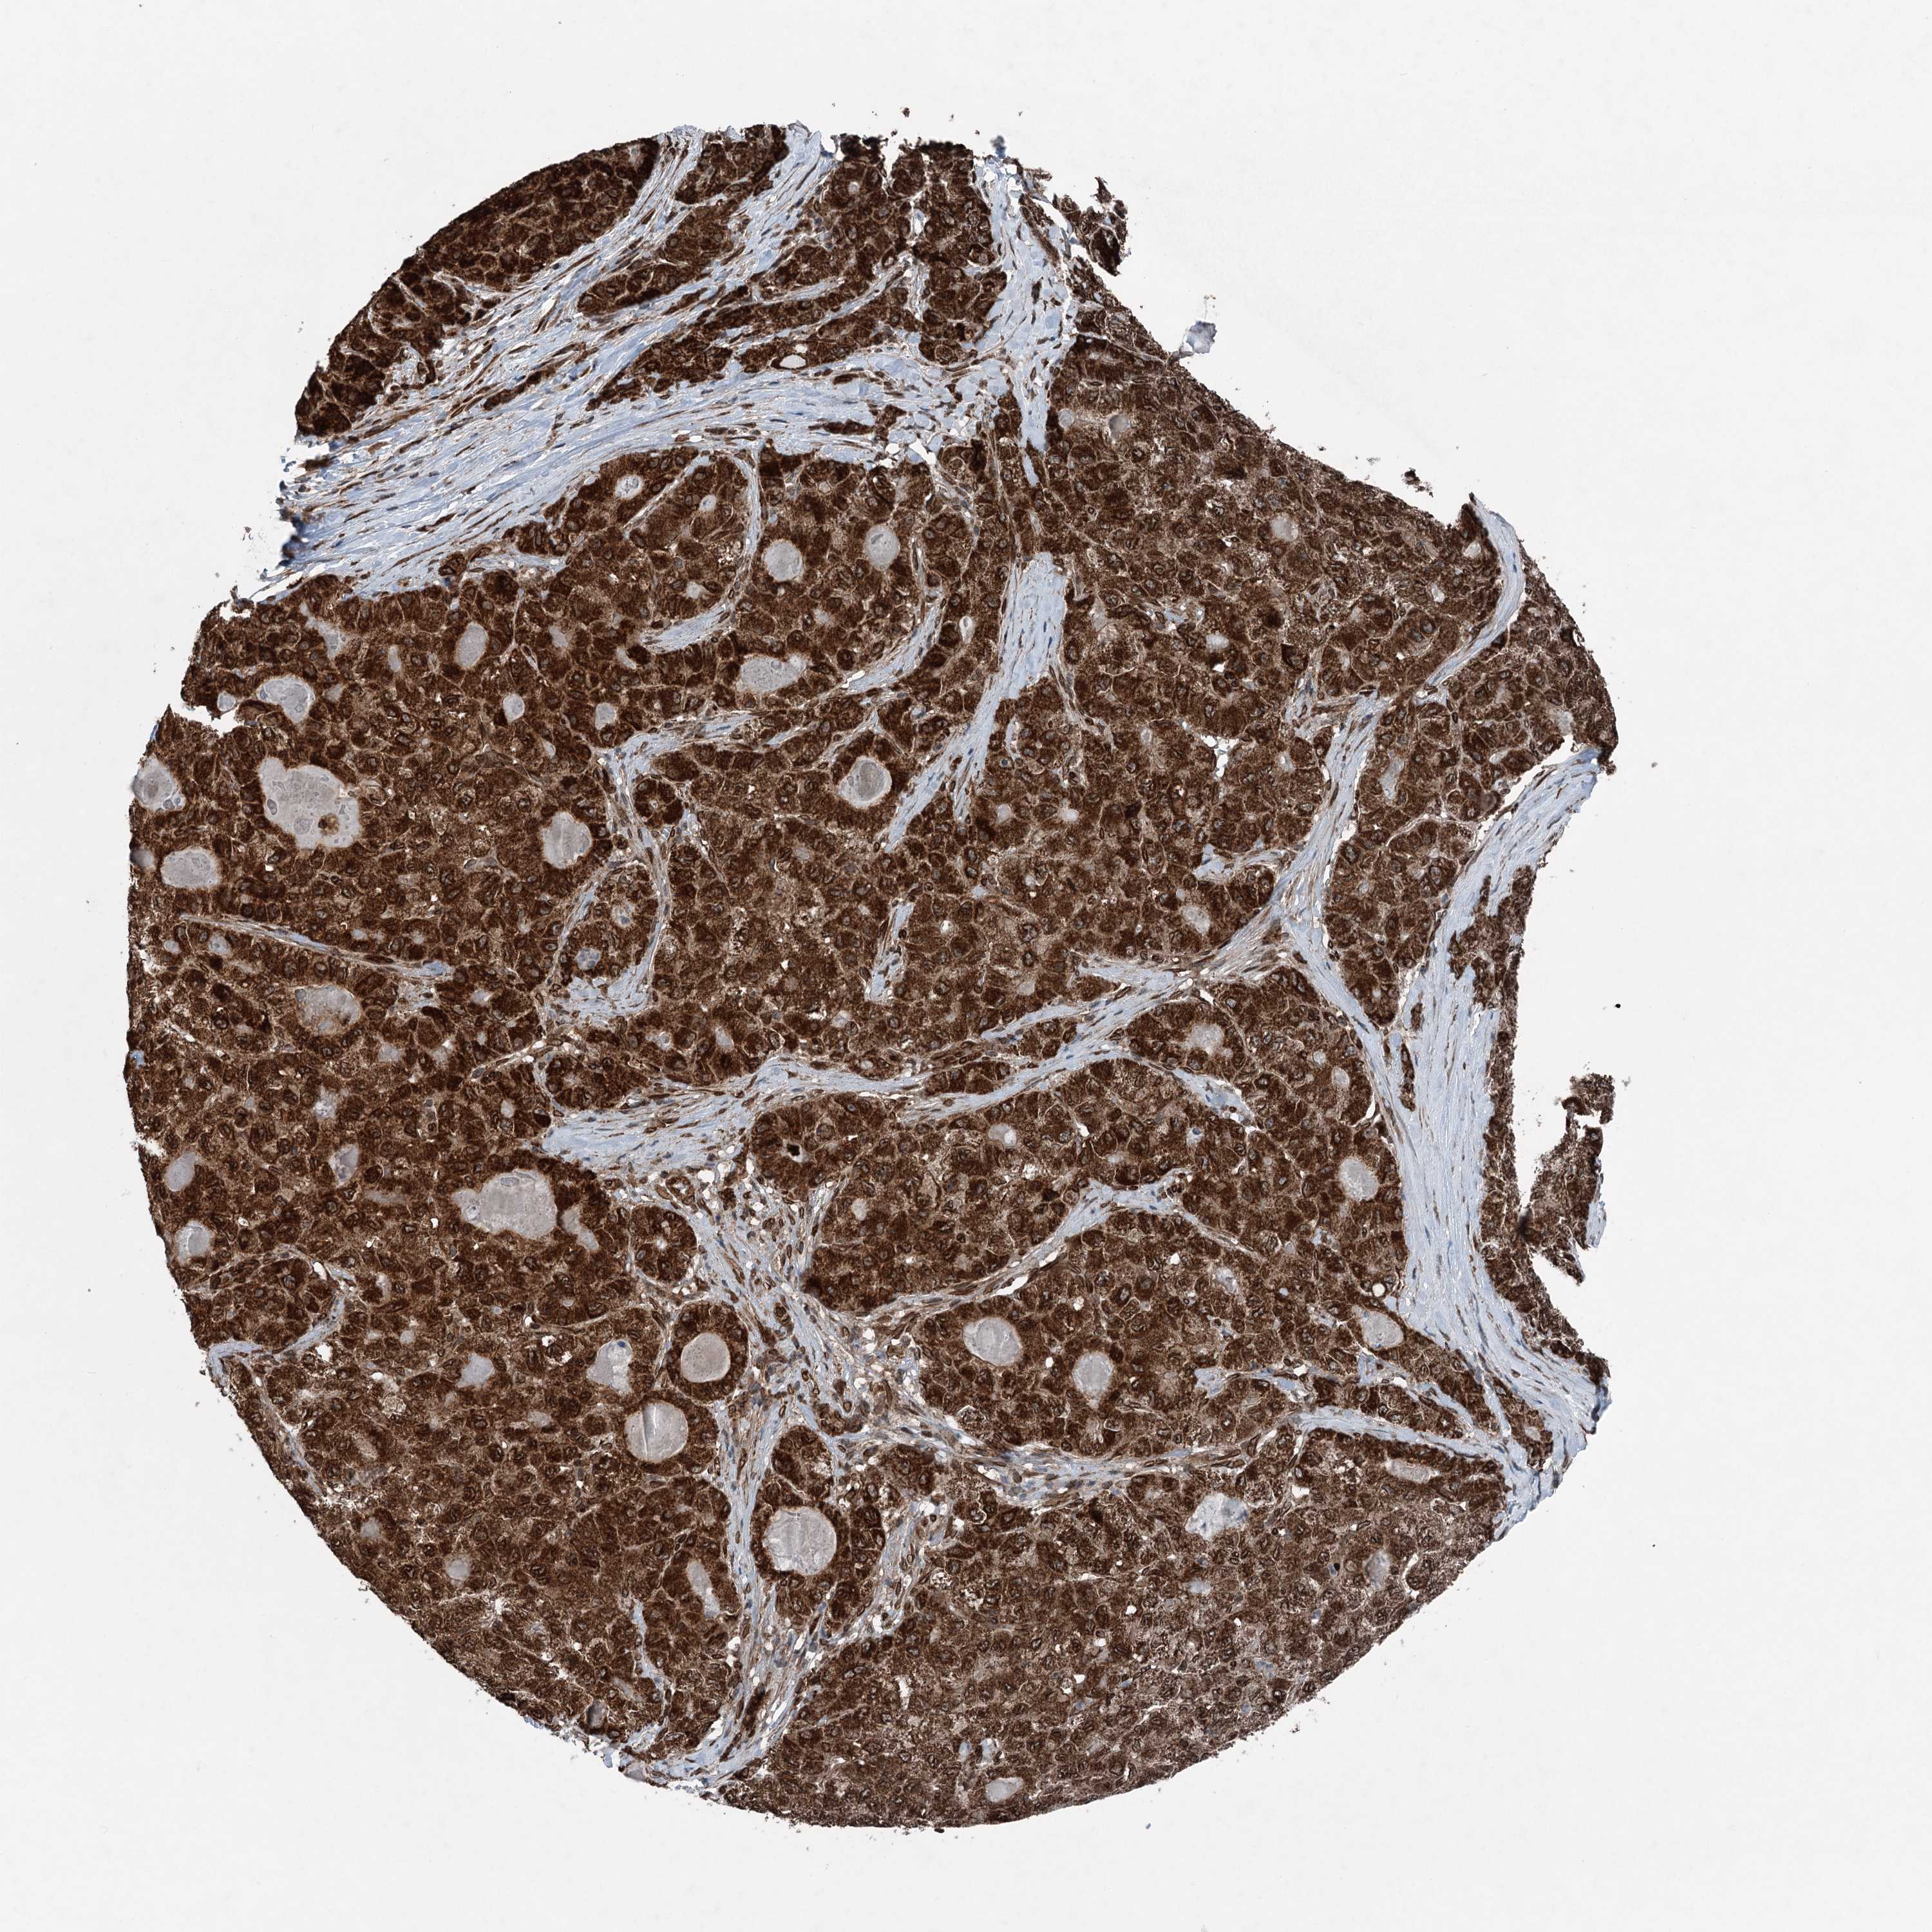

LIVER CANCER - Protein expressioni

A mouse-over function shows sample information and annotation data. Click on an image to view it in a full screen mode. Samples can be filtered based on level of antibody staining by selecting one or several of the following categories: high, medium, low and not detected. The assay and annotation is described here.

Note that samples used for immunohistochemistry by the Human Protein Atlas do not correspond to samples in the TCGA dataset.

Antibody stainingi

Antibody staining in the annotated cell types in the current human tissue is reported as not detected, low, medium, or high, based on conventional immunohistochemistry profiling in selected tissues. This score is based on the combination of the staining intensity and fraction of stained cells.

Each image is clickable and will lead to virtual microscopy that enables deeper exploration of all samples and also displays staining intensity scores, fraction scores and subcellular localization as well as patient and tissue information for each sample.

Antibody HPA036640

Staining

High

Medium

Low

Not detected

Intensity

Strong

Moderate

Weak

Negative

Quantity

>75%

75%-25%

<25%

None

Location

Nuclear

Cytoplasmic/membranous

Cytoplasmic/membranous,nuclear

Cholangiocarcinoma

Carcinoma, Hepatocellular, NOS